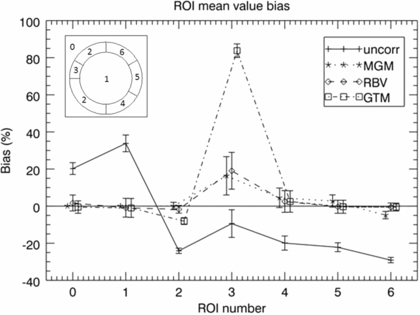

Figure 6 shows quantitative results, including the GTM results. Mean regional values were calculated for all the original phantom regions, and relative bias and the coefficient of variation (COV = SD/mean) values were obtained based on 30 noise realisations of the phantom. One conspicuous detail is the large bias obtained with GTM in ROI 3 (the unknown cold-spot). The voxel-based methods have a much lower bias, since they preserve the original image distribution within the regions. Even in ROI 2, MGM and RBV give a lower bias than GTM (for the same reason). In ROIs 4–6 all PVC methods have quite low bias, although this time MGM has a larger bias than GTM and RBV. This is because it does not correct for the cross-talk between different annular regions. The variability, given by the COV, is similar for all methods.

Figure 6. ROI analysis of phantom simulation from figure 5; the graph shows bias in different regions for the uncorrected image (plus-signs, solid line), and images corrected with the MGM (asterisks, dotted line), RBV (diamonds, dashed line), and GTM (squares, dot-dashed line) methods. The left inset shows the ROI number corresponding to each region in the phantom. The true relative activity concentrations for regions 0–6 were as follows: 0:0, 1:1, 2:4, 3:2, 4:3, 5:4, 6:8. The graph shows the bias relative to the true values for all regions except region 0, for which the absolute bias is presented. The error-bars represent regional COV values.